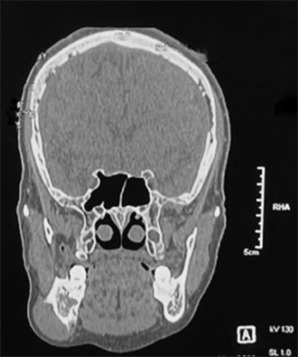

异位甲状腺是一种罕见的先天性异常,是由于胚胎发生阶段盲肠孔到原始甲状腺的管道失败而导致的。具体患病率为10 -30万分之一。发育、遗传和突变在异位甲状腺的形成中起作用。异位甲状腺最常见的位置是舌底,其次是下颌下、气管前、食管、纵隔、隔膜和其他罕见的部位。另外,侧异位甲状腺是一种罕见的临床疾病,它是由于甲状腺外侧部分未能下降到中线而形成的,正常解剖位置的正常甲状腺。在这里,我们提出一个病例报告的外侧异位甲状腺,通常不闪作为一个无痛的诊断标题,坚定的肿块在下颌骨的侧面,使治疗计划不确定。临床,放射学,实验室检查和组织病理学检查对异位甲状腺进行分类和最终治疗。定期随访并保持甲状腺功能正常,为患者提供了珍惜和积极的输出。

Ectopic thyroid is a rare congenital anomaly that results from failure of decent from the foramen cecum to the primitive thyroid during the stage of embryogenesis. The specific prevalence ranges from 1 in 100,000-300,000 population. Development, genetics, and mutation play a role in the formation of ectopic thyroid. The most common location of ectopic thyroid is at the base of the tongue, followed by sub-mandibular, pre-tracheal, esophageal, mediastinum, diaphragm, and other rare sites. Lateral ectopic thyroid is further a rare clinical entity which is formed due the failure of descend of the lateral thyroid component to the midline with a euthyroid in its normal anatomical position. Here, we present a case report of lateral ectopic thyroid which ordinarily does not flash as a diagnosis title for a painless, firm mass on the lateral aspect of the mandible, making the treatment plan inconclusive. Clinical, radiographic, laboratory tests with a histopathalogical examination make a categorical and final treatment for the ectopic thyroid. Regular follow-up with a euthyroid state maintenance gives a cherishing and positive output for the patient.